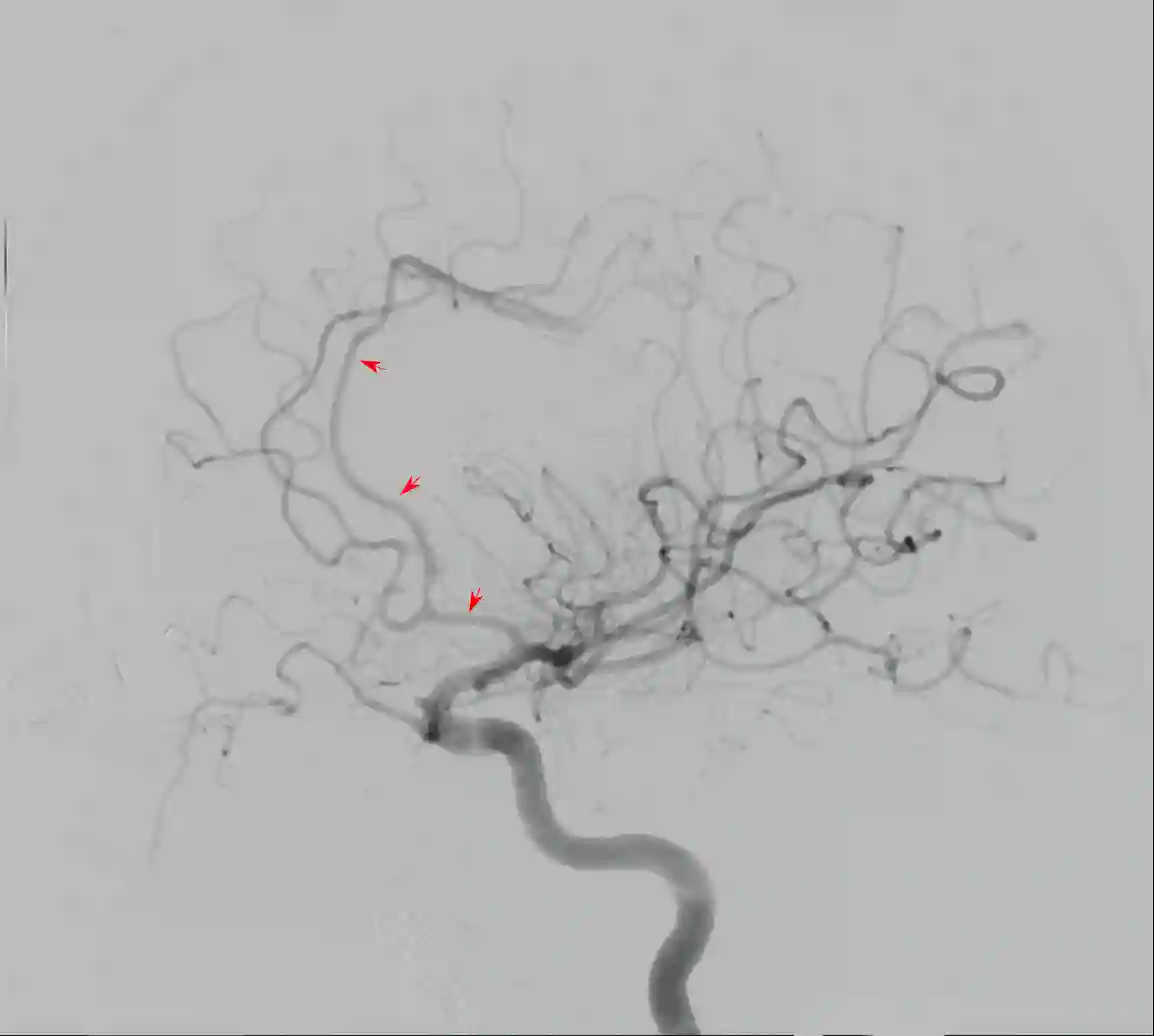

Arteria cerebri anterior DSA

Darstellung des Verlaufs der Arteria cerebri anterior (roter Pfeil) in einer lateralen digitalen Subtraktionsangiographie (DSA).